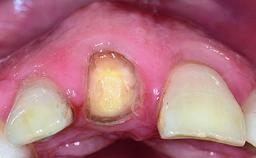

A 23-year-old female, healthy and non-smoking patient had had tooth 11 temporarily restored following a trauma in adolescence. As the patient’s growth had since come to an end and the crown had fractured, she requested an implant-supported restoration of tooth 11. Moreover, the contralateral tooth 21 presented an old composite restoration at the mesial incisal edge. The periodontal tissues were healthy with periodontal probing depth values below 3 mm, but some inflammation was observed around the semi-submerged root of tooth 11.